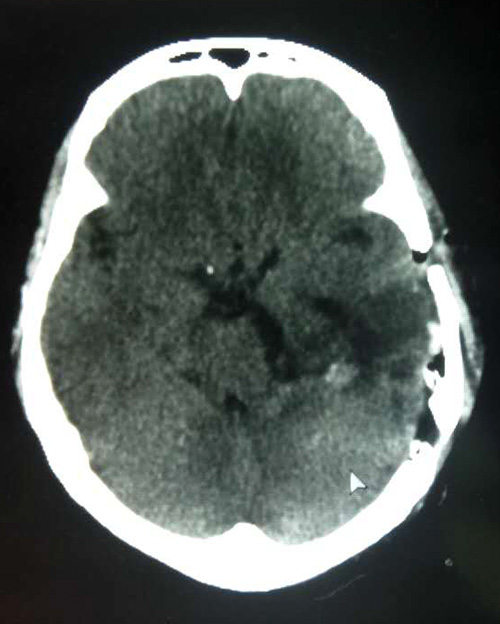

手術(shù)臺上,全麻狀態(tài)下的患者安穩(wěn)地沉睡著。沈建康教授眼前的腫瘤質(zhì)地柔軟,呈灰褐色。腫瘤已壓迫“生命中樞”腦干,所幸與腦供血動脈黏連并不緊密。沈建康教授憑借嫻熟的手術(shù)技藝,在醫(yī)院先進(jìn)的高倍顯微鏡下精雕細(xì)刻,輕輕牽拉、小心剝離,歷時約5個小時,分塊將腫瘤切除。術(shù)后通過CT復(fù)查,已不見腫瘤蹤跡,手術(shù)取得了成功。

▲患者術(shù)后CT已不見腫瘤蹤影